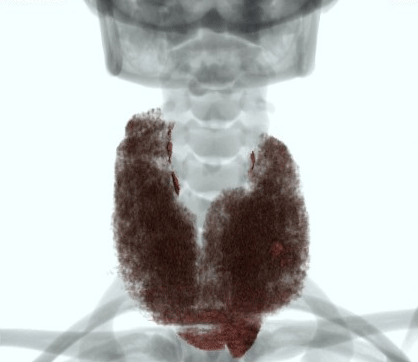

下記症例は19歳女性、甲状腺摘出術前で甲状腺容量測定の依頼があり、従来のCT装置では、Dual Energy撮影が出来なかったため、管電圧120kVで撮影していましたが、甲状腺の辺縁が同定しにくく、辺縁をトレースするのに苦労していました。Revolution CTが導入され、Dual Energy撮影が可能となり、低keVの画像を使用することで、甲状腺のCT値が上昇し境界が明瞭になり、容量測定が容易になりました。

RevolusionCT_Sapporotokusyuukai_04.png

70keV

RevolusionCT_Sapporotokusyuukai_05.png

40keV

RevolusionCT_Sapporotokusyuukai_06.png

VR画像